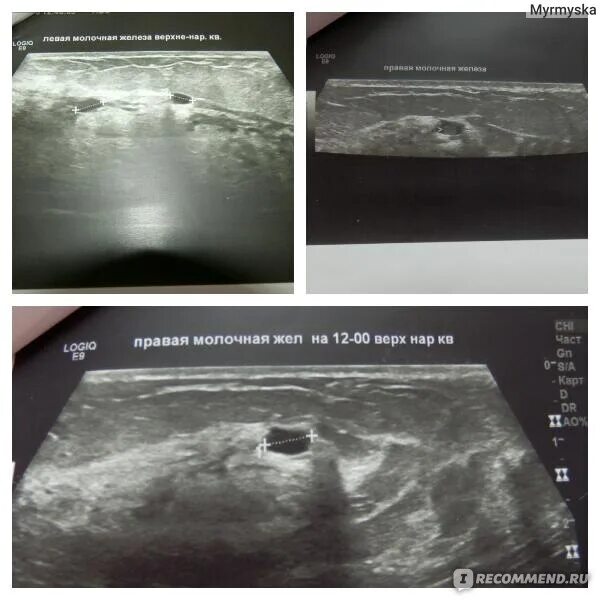

Вакуумное удаление фиброаденомы молочной